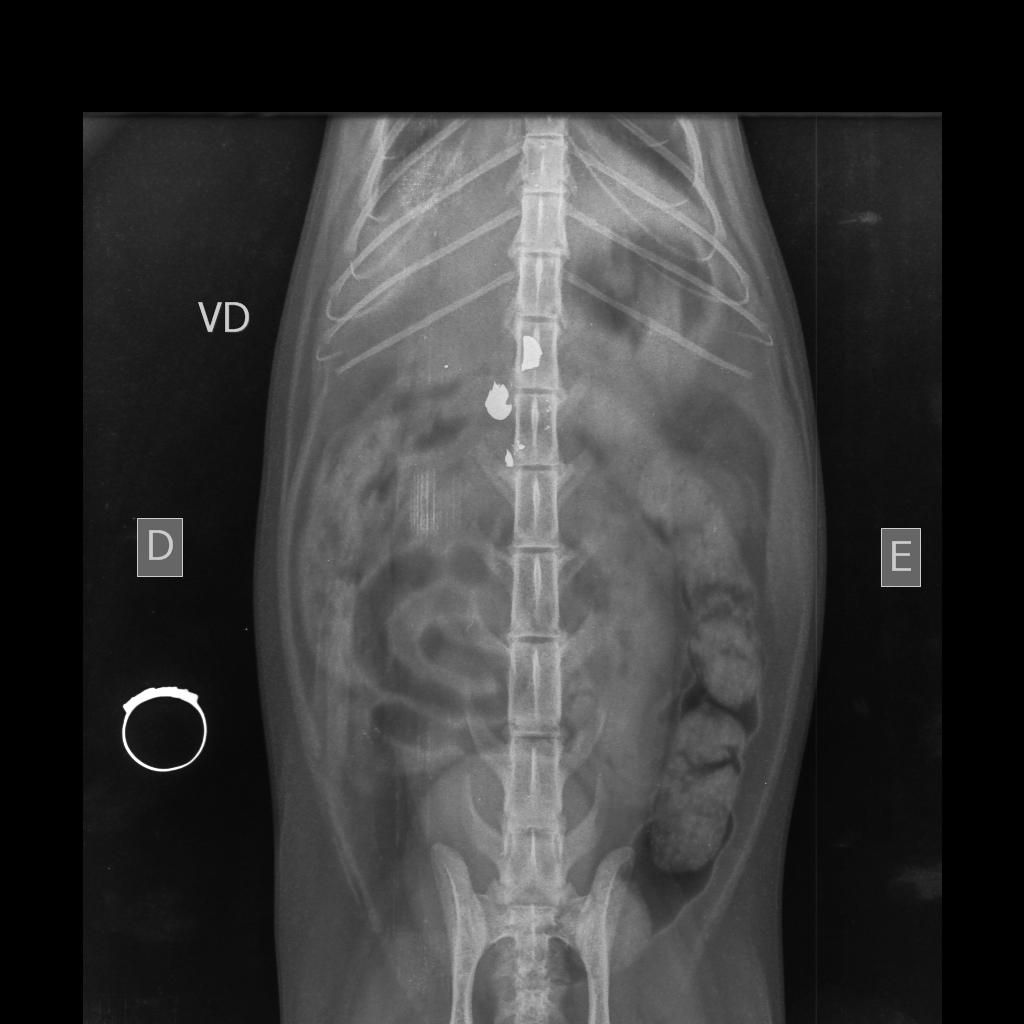

A Polícia Civil investiga mais um caso de agressão contra animal em Toledo. Na madrugada de terça-feira (03), por volta das 0h07, uma gata foi atingida por um disparo no bairro Jardim La Salle.

De acordo com o delegado Dr. Alexandre Macorin, os proprietários do animal já foram ouvidos e a gata está sendo submetida a cirurgia. Testemunhas também foram identificadas, e o provável autor do disparo deverá ser ouvido e interrogado nas próximas horas.